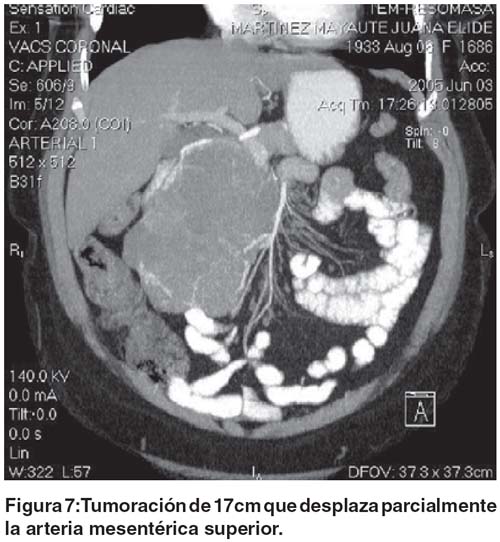

Se solicita una tomografía espiral multicorte, con cortes ultra finos para definir resecabilidad, donde se evidencia tumoración quística gigante de cabeza de páncreas de 17 X 13 X12 cm. que esta en estrecho contacto con la arteria y la vena mesentérica superior en toda su extensión. (Fig.: 5-8) Se programa a la paciente con el diagnostico de cistoadenoma seroso del páncreas.